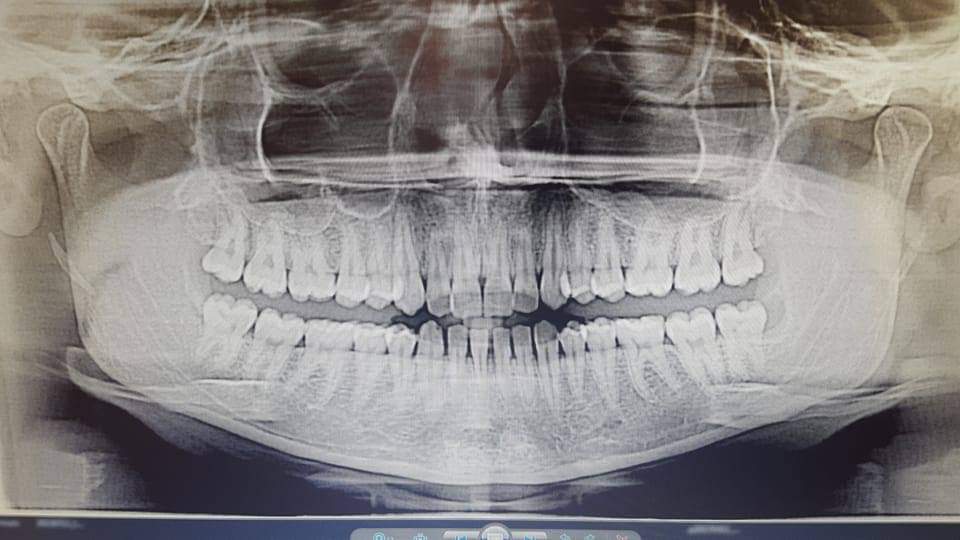

2.وتكمن الحالة الثانية لإمرأة تبلغ الرابعة والعشرين 24 من عمرها وتتمتّع بمجموعة كاملة من الأسنان السليمة القويّة( 32 سنّ)